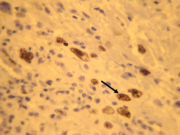

Carcinoma mucoepidermoide de grado intermedio de malignidad. Inmunohistoquímica Ki 67 positiva (flecha).